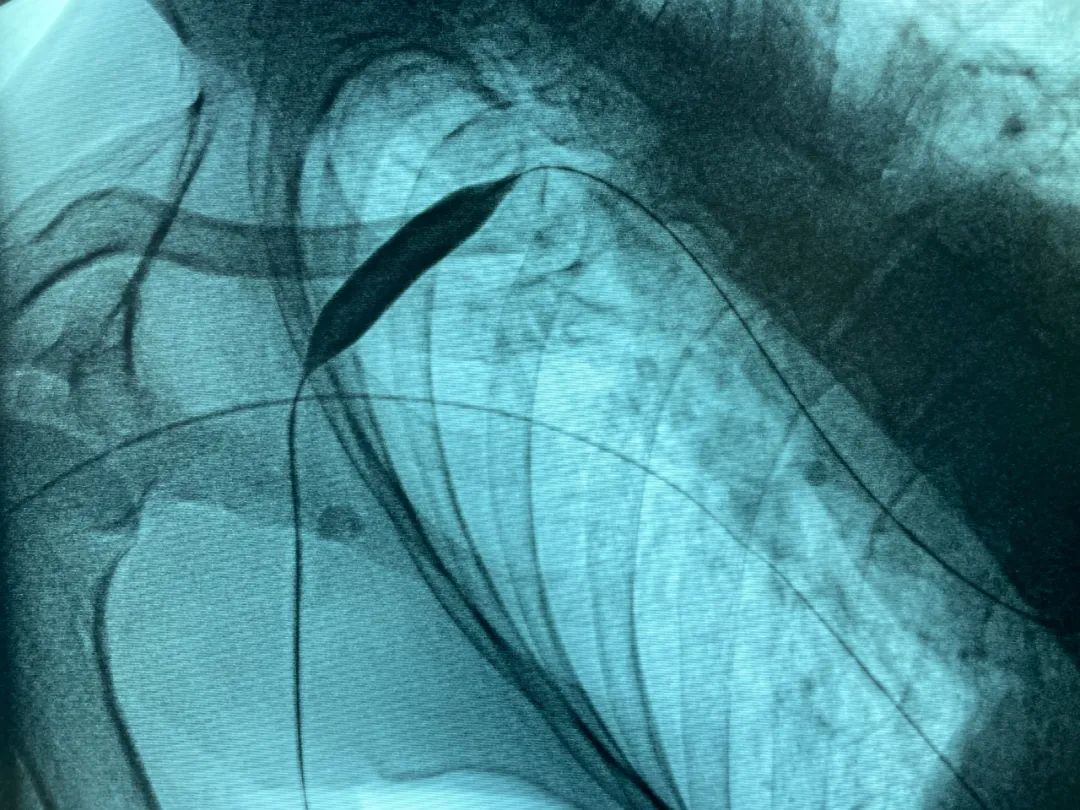

病变明确了,张东亮很快为金大叔在介入手术中心安排了局麻下经皮穿刺血管腔内治疗。(图2)球囊扩张前造影,可见腋静脉血流缓慢,侧支循环形成。(图3,4)将球囊定位至狭窄处,反复充分扩张,可见切迹(狭窄)消失。(图5)再次造影,血流通畅、增快,侧支循环和返流消失。整个手术过程仅持续半个小时。

图4

图5